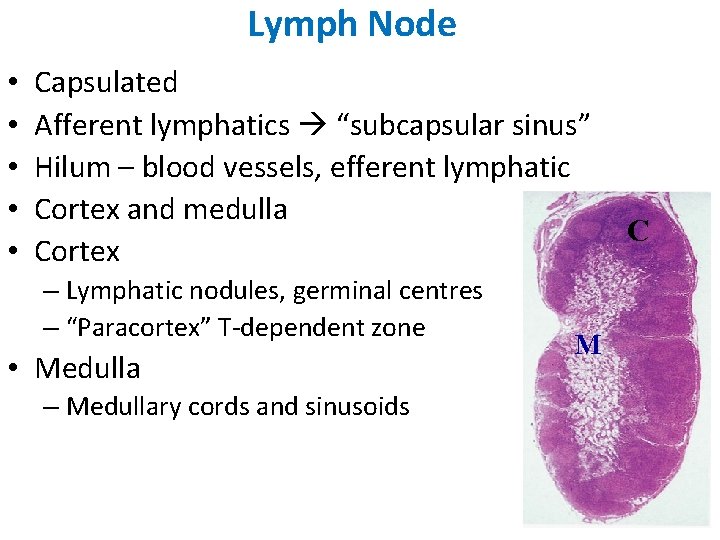

Lymph Node • • • Capsulated Afferent lymphatics “subcapsular sinus” Hilum – blood vessels, efferent lymphatic Cortex and medulla Cortex – Lymphatic nodules, germinal centres – “Paracortex” T-dependent zone • Medulla – Medullary cords and sinusoids M C

LYMPH NODES These are the smallest but most numerous encapsulated lymphoid organs. Scattered in groups along lymphatic vessels , they act as in-line filters of the lymph, removing antigens and cellular debris and adding Igs. Lymph nodes are bean-shaped structures with convex and concave surfaces. The parenchyma consists of a peripheral cortex, adjacent to the convex surface, and a central medulla lying near the depression (hilum) in the concave surface. The connective tissue capsule gives off trabeculae that penetrate between the cortical nodules and subdivide the cortex. Cortex. The cortex is dark-staining owing to the presence of tightly packed lymphocytes. These are suspended in a reticular connective tissue network and arranged as a layer of typical secondary lymphoid nodules (containing primarily B lymphocytes) with germinal centers. The cortex also contains reticular cells, antigen-presenting follicular dendritic cells, macrophages, a few plasma cells, and some helper T cells.

Medulla. Lighter staining than the cortex, the medulla is composed of cords of lymphoid tissue (medullary cords) separated by medullary sinuses. The lymphocytes are mainly small, less numerous than in the cortex. The cords are also rich in reticular cells and fibers and contain many plasma cells that have migrated from the cortex. Paracortical zone. This is the T-dependent region, lying between the cortical lymphoid nodules and the medulla. It contains mainly T lymphocytes suspended in a reticular connective tissue. B lymphocytes, plasma cells, macrophages, and antigen-presenting interdigitating dendritic cells may also be present. Lymphatic vessels. Sinuses (subcapsular, peritrabecular, medullary). Functions: 1. Filtration of lymph 2. Lymphocyte production (lymphopoiesis). 3. Immunoglobulin production.